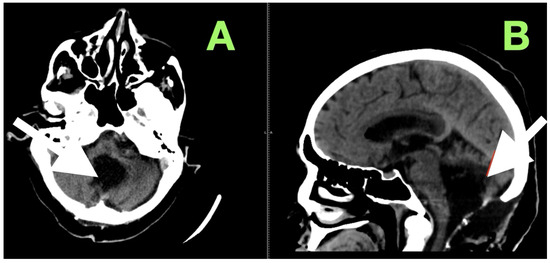

After extubation in the neurosurgical ICU postoperatively, early recovery included trunk stability, improved gaze-holding nystagmus, and less dysmetria. There were no cranial nerve impairments noted, and swallowing remained safe. Postoperative CT (Figure 3) confirmed complete decompression and re-expansion of the fourth ventricle, patency the cerebellomedullary cistern, symmetric cerebellar hemispheres, and patent foramen of Magendie. There was no presence of hemorrhage, infarction or hydrocephalus, and the operative cavity duplicated the original tumor size, underscoring the painstaking extra-axial dissection while maintaining parenchymal margins.

Figure 3. Immediate postoperative non-contrast CT scan demonstrating complete removal of the fourth-ventricular epidermoid tumor and restoration of posterior fossa anatomy. (A) Axial view shows a well-defined postoperative cavity in the midline vermian and fourth-ventricular region, with full re-expansion of the fourth ventricle and reappearance of the cerebellomedullary cistern. The brainstem contour is normalized, and no residual mass effect or obstructive hydrocephalus is present. (B) Coronal reconstruction confirms symmetrical cerebellar hemispheres, midline restoration of the fourth ventricle, and patent foramen of Magendie, with no acute hemorrhage or postoperative edema. The surgical cavity follows the anatomical boundaries of the preoperative lesion, reflecting precise extra-axial microsurgical dissection and preservation of surrounding neural tissue.